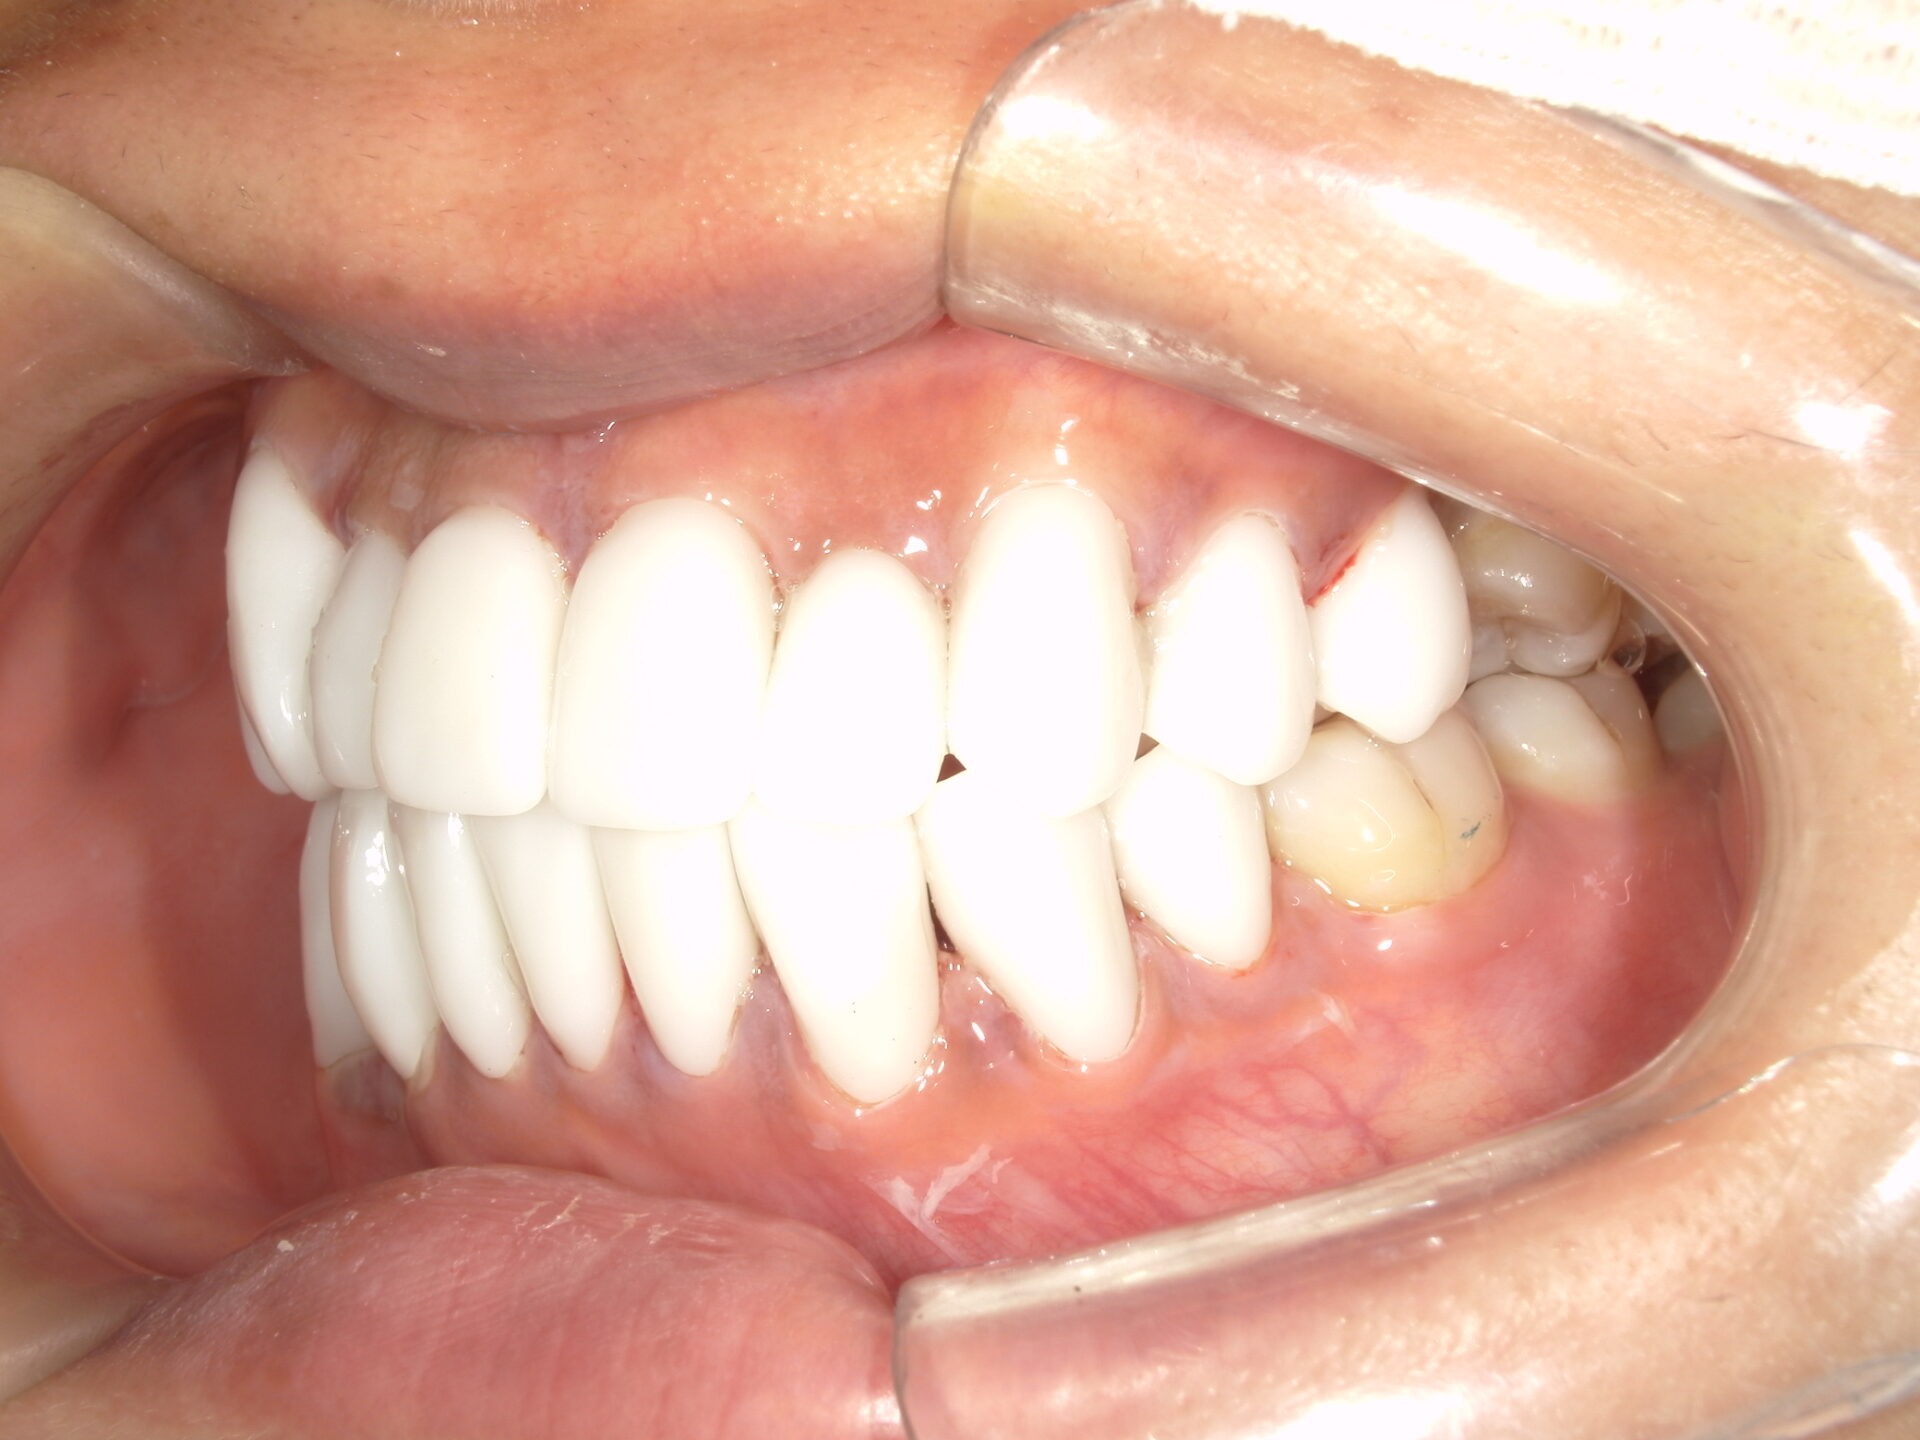

after

患者さんの年齢 20代 女性 症状 ガタガタを治したい 治療内容 マウスピース矯正治療 費用 90万(税抜) 治療期間・回数 治療期間2年、通院回数10回 メリット 笑顔が綺麗 デメリット・リスク 期間がかかることがある - マウスピース矯正